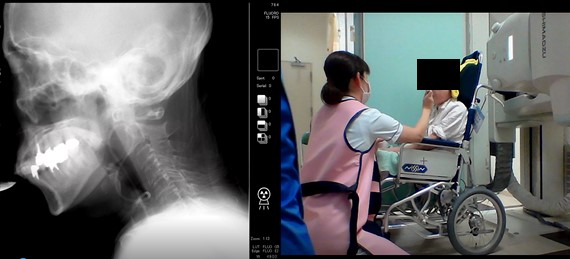

摂食機能療法

食物を食べたり、水分を飲んだりすることの障害である「摂食嚥下障害」に対して、食事評価(姿勢調整、食形態、とろみの濃度、一口量、介助方法など)や練習を行い、安全に食べることができるようにアプローチします。また必要に応じて、レントゲン透視下による嚥下造影検査も実施しています。